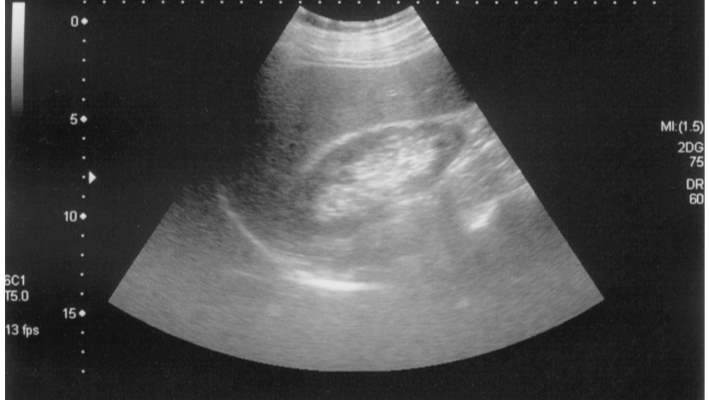

Anneme cekilen tomografide karaciger buyuklugu normaldir. Karaciger parankim dansitesu normalden dusuktur.(hepatosteatoz). Intrahepatik safra yollari ve vaskuler yapilar tabidir. Safra kesesinin volumu, duvar kalinligi normaldir. Safra kesesi boynunda 4 mm ve fundusta 8 mm boyutunda hiperdens kalkuller izlenmistir.safra kesesi bilobule gorunumdedir. Koledok capi normal genisliktedir.dalak buyuklugu normal olup, parankim danaitesi homojendir.pankreas ve paraaortik alanlar tabii izlenmektedir.her iki bobrek parankim dansitesi,toplayici sistemleri tabidir.bilateral surrenal glamdlar tabiidir. Mesane homojen izlenmektedir.batin ici sivi serbest sivi izlenmemiatir. Sol overde 4.5 cm boyutunda hipodena kist izlensi. Umblikal herni izlendi. ( hocam durum nedir )